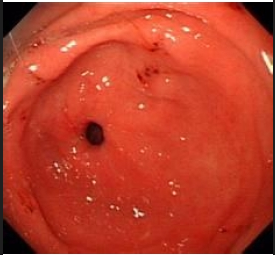

l由于慢性胃炎发病缓慢,早期症状缺乏特异性,甚至患者觉得毫无症状,常常能不引起人们的重视。因此,了解慢性胃炎的相关症状很有必要。那么,慢性胃炎都会出现哪些症状呢?

症状一:中上腹不适,饱胀、钝痛、烧灼痛。尤其是在进食后症状比较重,同时还会出现食欲不振、嗳气、泛酸、恶心、气顶胸闷、打嗝。少数患者会无明显临床症状,也有的患者会出现头晕眼花、失眠、贫血等并发症。

症状二:上腹疼痛、隐痛。大多数在空腹时比较舒适,吃饭后疼痛较为明显不适。吃冷食、硬食、辛辣或其它刺激性食物,会诱发发病,进一步加重病情,有的天气寒冷也会诱发发病,所以要注意保暖。